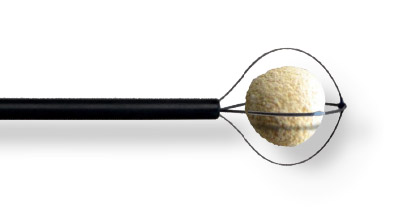

Excellent memory and flexibility

Minimal trauma and Bleeding

With tuohy borst connected, allowing 272μm Fiber to be introduced

| Reference | Description | Ø (Fr) | Wire | Working Length (cm) | Basket Ø (mm) | Basket Length (mm) |

|---|---|---|---|---|---|---|

| ROKP1001ST | PerkX Coaxial PCNL Stone Extractor for Rocamed Laser Fiber max 272μm | 10 | 4 | 38 | 20 | 17.5 |